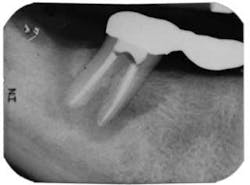

Endodontic case study: Healing of a large lesion in a lower molar after proper dental instrumentation and irrigation

Diagnosis: Pulpal necrosis with chronic periradicular abscess

Clinical evaluation revealed a draining fistula on the buccal aspect of tooth No. 31. Endodontic testing revealed tooth No. 31 had no response to cold, no pain to percussion, 7-8 mm probing depths on its distal aspect, and pain on palpation. All other teeth in the quadrant tested normal. The diagnosis was pulpal necrosis with chronic periradicular abscess. The patient was advised that the prognosis was guarded, but if she wanted to try to save the tooth, we could try.

The patient was anesthetized using two carpules of 2% lidocaine for IANB and two carpules of Septocaine for long buccal infiltration. The tooth was isolated with a rubber dam and accessed under a dental operating microscope using long shank round burs and an Endo-Z bur for refining the access to cavity walls. Working length was determined using Root ZX II electronic apex locator. Instrumentation was completed using Xgates, and a combination between Protaper and Vortex Blue files with full-strength sodium hypochlorite irrigation. QMix was placed into the canals after irrigation and agitated with EndoActivator to remove the smear layer and for its antibacterial properties. Calcium hydroxide was placed, and the root canal was temporized with TERM temporary.